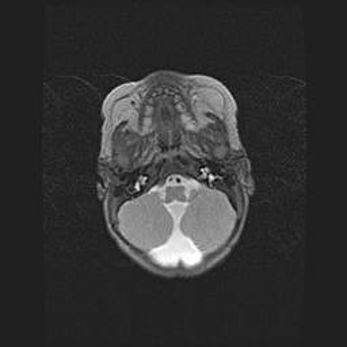

Мальформация Денди-Уокера. Киста задней черепной ямки.

Агенезия мозолистого тела.

Возраст: 2,5 месяца

Вес: 2420 г

Пол: женский

Окружность головы: 37 см

Срок гестации: 32 недели

Мальформация Денди—Уокера — редкий вид патологии ЦНС, представляющий собой врожденный порок развития каудального отдела ствола и червя мозжечка, ведущий к неполному раскрытию срединной (Мажанди) и латеральных (Лушка) апертур IV желудочка мозга. Для этогно синдрома характерна триада симптомов: гипотрофия червя мозжечка и/или полушарий мозжечка, кисты задней черепной ямки, гидроцефалия различной степени. В 70% случаев порок сочетается и с другими аномалиями головного мозга, в частности с агенезией мозолистого тела.